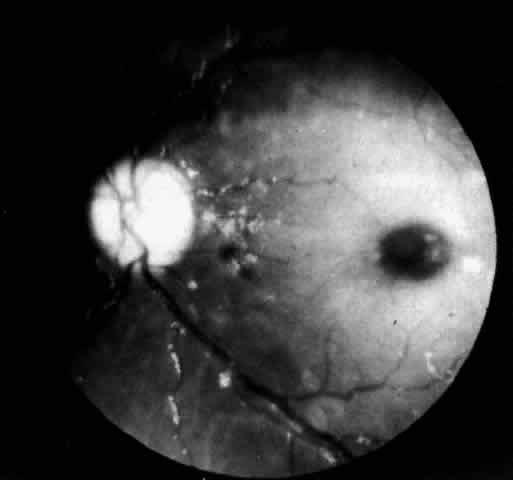

A more widespread opacification of the retina can occur due to involvement of the ganglion cells in the posterior pole. This was observed by Wray4 in a 3½-year-old child with Tay-Sachs disease. The child had black hair and brown eyes, and the cherry-red spot at the macula was brown. The patient was blind, with marked optic atrophy (Fig. 4).

Fig. 4. Fundus of 3 1/2-year-old girl with Tay-Sachs disease. Note cherry-red spot, an extensive white parafoveal halo, and optic atrophy.

In three patients with type III subacute juvenile neuronopathic Gaucher's disease however, the retina showed a unique retinopathy. The findings in Cogan's case 1 are described: “Both fundi showed discrete white spots randomly distributed in the posterior fundus, especially along the inferior vascular arcades (Fig. 8). The spots varied in diameter from just visible to approximately 0.1 mm and were situated in the superficial retina or on the surface of the retina. Several covered the retinal vessels. The disc and retinal vessels were normal.” The child, an 11-year-old boy, had normal acuity and a full field of vision by confrontation. He had presented at age 3 years with splenomegaly.

Fig. 8. Fundus of a patient with type III subacute juvenile neuronopathic Gaucher"s disease showing discrete white spots in or on the retina along the inferior vascular arcades. At least one spot overlies a vein. The optic disc and retinal vessels were normal. (Cogan DG, Chu FC, Gittinger J, Tyshsen L: Fundal abnormalities of Gaucher"s disease. Arch Ophthalmol 98:2202, 1980. Copyright © 1980, American Medical Association)